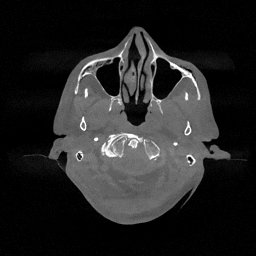

The results for simulated noisy data are shown in Fig. 2. The first and third rows display two representative slices from the test set, and the second and fourth rows present the corresponding error maps. The traditional WCE method suppresses cupping artifacts and recovers some missing anatomical structures but still shows noticeable deviations from the ground truth. Predictions from the four diffusion-based models demonstrate a markedly improved ability to restore anatomical structures. Among them, cDDPM fails to fully reconstruct the patient bed and retains residual noise in its outputs. This noise is attributable to an incomplete reverse denoising process rather than residual Poisson noise, as evidenced in our noise-free experiments (Fig. 5 in the Appendix). PatchDiffusion, diffusionGAN, and I2SB achieve similar visual quality, with I2SB producing the cleanest and most consistent reconstructions.

The experimental results on clinical head data are shown in Fig. 4. The reference images were reconstructed using the fast iterative shrinkage-thresholding algorithm (FISTA) with total variation regularization from non-truncated projection data. In the WCE reconstructions (Fig. 4(b)), severe truncation prevents accurate recovery of anatomical structures outside the FOV. Despite being trained solely on simulated data with a domain gap, all deep learning models can restore a substantial portion of the missing anatomy. Among them, the diffusion-based methods recover soft-tissue boundaries more faithfully than the conventional deep learning approach FBPConvNet, highlighting their stronger image generation capability. However, cDDPM reconstructions exhibit more noticeable noise than those from other methods, consistent with the simulated data results. The patchDiffusion model introduces artifacts within the FOV, likely due to its patch-wise processing strategy. While I2SB shares the same limitations as other diffusion models in perfectly restoring soft-tissue detail, it produces fewer residual noise patterns and fewer artifacts within the FOV boundaries. Overall, Fig. 4 demonstrates the strong efficacy of I2SB in reconstructing real CBCT data.